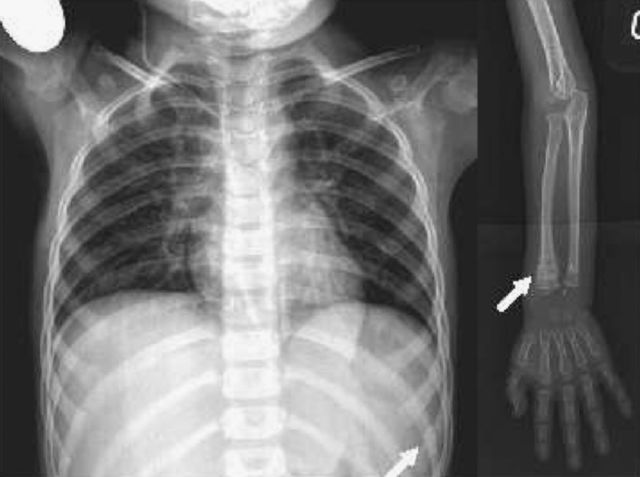

Se publicaron los hallazgos de fracturas múltiples y hematomas subdurales en 6 niños.

describió lo que llamó "Traumatismos Esqueléticos no reconocidos" y sugirió que muy posiblemente los padres eran los

autores.

el maltrato físico infantil es la generación, el desarrollo y/o promoción activa de conductas, sucesos y/o situaciones bajo el control de los padres que se traducen en lesiones físicas intencionales causadas a un menor de 18 años